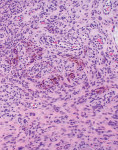

An excisional biopsy of the lesion was performed, and the specimen was submitted to a pathology laboratory. The results of the histologic analysis are shown in Figure 3 and Figure 4.

Routine microscopic analysis of PGCG reveals the presence of an abundance of multinucleated giant cells with ulcerated granulation tissue, which is a distinctive feature of PGCG (Figure 4).1 Evidence of fusion of blood monocytes forming osteoclastic multinucleated giant cells is also characteristic of PGCG (Figure 4 and Figure 5), consistent with profuse hemorrhage observed within the mass. Additionally, the presence of brown pigmentation within the histologic specimen correlates with the presence of hemosiderin and is a hallmark feature of PGCG (Figure 5).1